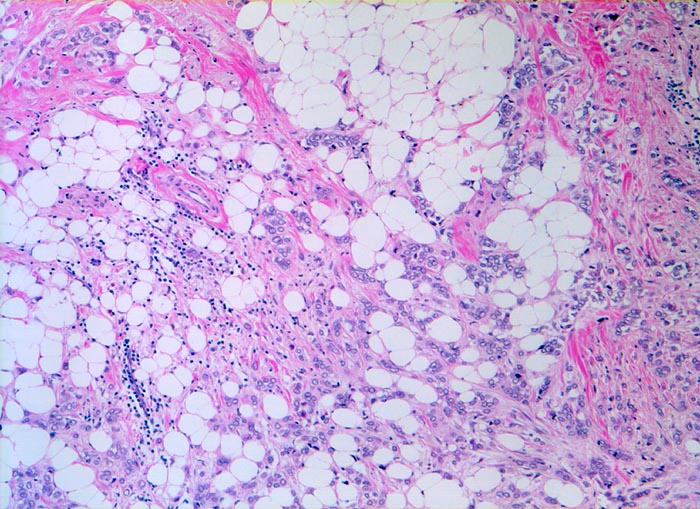

Invasiv lobuläre Karzinome sind in bis zu 80% mit einem lobulären in situ Karzinom und in 36% der Fälle mit einem duktalen Karzinom (in situ oder invasiv) assoziiert. Ein Viertel der Tumoren wächst multizentrisch. Das klassische invasive lobuläre Karzinom besteht aus kleinzelligen monomorphen Infiltraten, welche anstelle von Drüsen einreihige Tumorzellstränge bilden. Diese wachsen zirkulär um vorbestehende Drüsenläppchen (> 4221)und durchsetzen den Drüsenkörper diffus. Oft lassen sich intrazelluläre muzinhaltige Zytoplasmavakuolen nachweisen, die wie Siegelringzellen (> 4224) imponieren. Die Tumorzellen induzieren eine ausgeprägte desmoplastische Bindegewebsvermehrung.

Morphologische Merkmale:

• Multifokale Infiltrate eines invasiv lobulären Mammakarzinoms: Kleine monomorphe, zytoplasmaarme Tumorzellen bilden einreihige Ketten (gänsemarschartig = Indian files) oder sind konzentrisch um nicht neoplastische Drüsen angeordnet.

• Das Karzinom bildet keine Drüsen.

• Zytologisch blande Tumorzellen mit kleinen runden hellen Kernen.

• Reichlich dichtes desmoplastisches Tumorstroma.

• Lobuläre Neoplasie (=nicht invasiver intralobulärer Karzinomanteil): Neben den zystisch erweiterten Drüsen finden sich Mammaläppchen, deren Azini teilweise leicht vergrössert sind durch Ansammlungen von atypischen Zellen mit vergrösserten Kernen und prominenten Nukleolen. Die Basalmembran der tumorbefallen Azini ist erhalten.